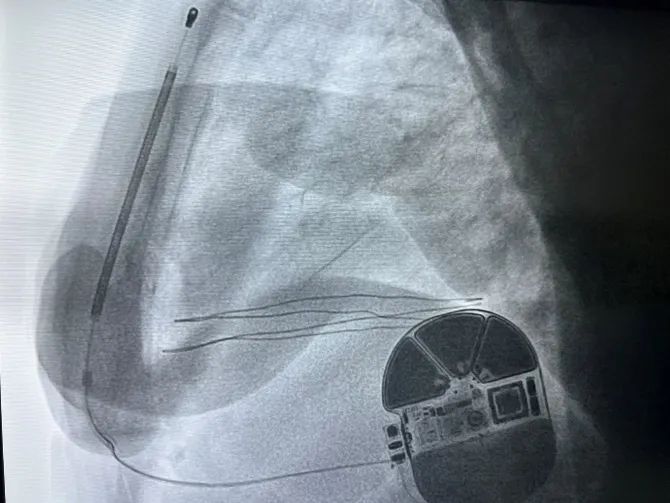

由心外科、介入室、麻醉科协作,手术在基础麻醉(镇痛)下进行,于患者左侧第5肋间沿腋中线走形切开皮肤6cm至7cm,逐层分离至皮下,分离囊袋至背阔肌与前锯肌之间。再次于剑突左上缘1cm为预定点,切开皮肤3cm,逐层分离皮下组织至筋膜层,并预埋两根缝合线,通过皮下隧道器将电极从横切口导引至囊袋,在横切口处固定电极;接着用隧道器导引除颤电极于深筋膜层至胸骨上窝位置,对所有伤口区进行有效止血,同时通过按压将隧道内空气排出,防治导线的感知受到影响。随后连接除颤装置,置入囊袋内,逐层缝合皮下组织及皮肤,术区纱布覆盖,包扎,弹力绷带加压包扎止血。

由于患者房颤,且基础情况较差,经专家讨论后决定不予术中诱颤,术后PRETORIAN评分小于30分,DFT成功率极高。